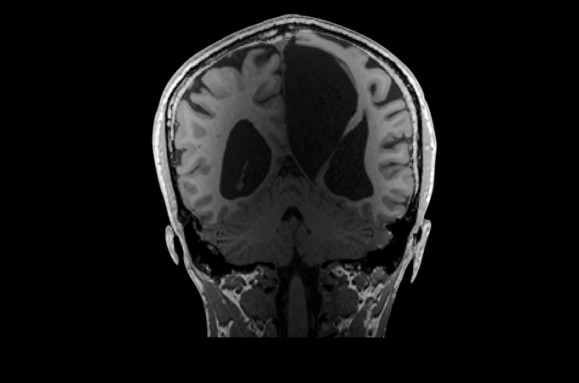

Elyse G. found out she lacked most of her left temporal lobe when she was 25 years old. The brain region is typically crucial for speech and language — but until her brain was scanned (three views shown), no one knew Elyse was missing hers.

Looking at her brain scans is a different story. It’s as if someone has knocked over a bottle of ink. The darkness pools inside her skull near her left ear, a puddle of fuliginous black. Inside the splotch, there’s no white matter or gray matter, no blood vessels or tissue at all.

Elyse says you don’t have to be a neurosurgeon to spot what’s different about her brain: “There’s a big honking piece missing!”